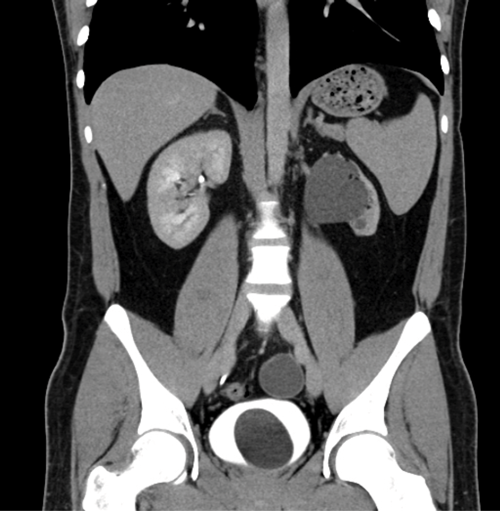

Case 4

- A CT urogram has been undertaken with contrast seen in both collecting systems. A CT cystogram was performed at the same time, with contrast instilled into the urinary bladder via existing Foley catheter. This allows assessment of both the upper tracts and the bladder to look for any injury following trauma. Contrast should be used at a concentration of 10% during CT cystogram, otherwise the contrast opacification will be too dense and make interpretation difficult.

- There is abnormal contrast opacification seen superiorly to the urinary bladder, within the peritoneal cavity.

- Findings are in keeping with an intraperitoneal bladder rupture. This is seen in approximately 15% of major bladder injuries and is usually caused by direct trauma to a distended bladder. The axial CT image demonstrates fluid, some of which has opacified with contrast, in the peritoneum.

- Surgical repair is required for intraperiteonal bladder rupture. Extraperitoneal bladder rupture is more common, accounting for 80-90% of cases, and is usually due to penetrating trauma or as a result of pelvic fractures. Treatment of an extraperitoneal bladder rupture is conservative, with a Foley catheter left in situ until the rupture heals.